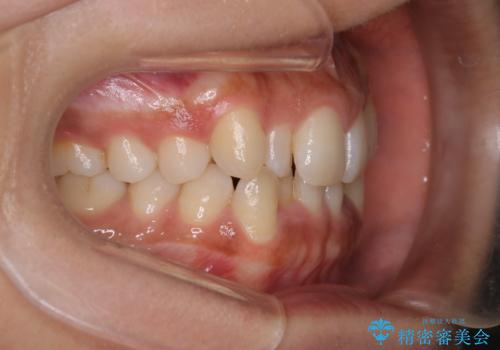

反対咬合と前歯のガタガタを非抜歯で改善

- 患者様は、上下の前歯のガタガタと反対咬合(下の歯が上の歯より前に出ている状態)を主訴として来院されました。診断の結果、抜歯を行わずに治療を進めるため、臼歯を遠心移動させてスペースを作り、IPR(インタープロキシマルリダクション)で歯間を調整する治療計画を立てました。インビザラインを使用して、透明で目立たない矯正装置により、歯列を整えながら噛み合わせも改善することを目標としました。

非抜歯での治療では、限られたスペースの中で効率的に歯を動かす必要があります。本症例では、臼歯を後方に移動させる遠心移動を行い、歯列のガタガタを改善しました。また、IPRを適切に行うことでスペースを確保し、歯根や歯肉への負担を最小限に抑えながら治療を進めました。インビザラインを使用することで、治療中も目立ちにくく、患者様の日常生活への影響を軽減しました。結果として、抜歯を行わずに美しい歯並びと自然な噛み合わせを実現し、患者様には大変満足していただけました。